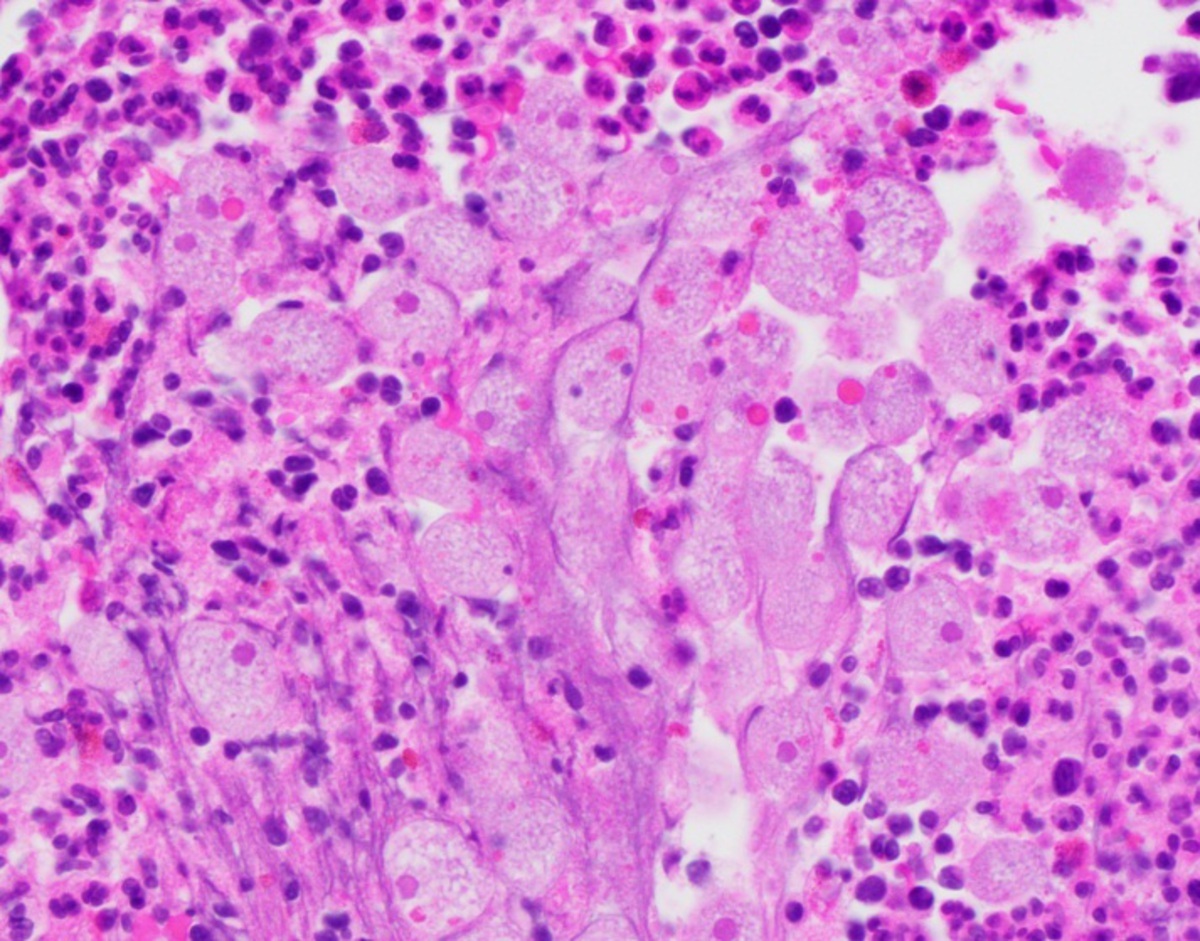

A 55-year-old female smoker with no significant past medical history presents with left lower quadrant abdominal pain over the last 3 months. She has had recent constipation with intermittent rectal bleeding and notes that her pain is worse with bowel movements. She has never had a colonoscopy. On exam, she is afebrile and has mild left and right lower quadrant tenderness to palpation with mild guarding and no rebound. During colonoscopy, her Boston bowel prep score is 3 and visualization is difficult. She has distal sigmoid edema and narrowing which cannot be traversed despite multiple attempts. A biopsy of the sigmoid colon is shown in the figure. The scope is withdrawn and in recovery, the patient has worsening abdominal pain. What should you do next?

This patient has classic findings of diverticulitis. Up to 15% of patients with diverticulosis develop diverticulitis. Tobacco use is an independent risk factor of diverticulitis. Diverticulitis is a micro or macro perforation of a diverticulum. A subset of patients develop smoldering diverticulitis and can have subacute prolonged symptoms of abdominal pain, rectal bleeding, and change in bowel habits that can last over 6 months. Abdominal imaging, preferably computed tomography (CT) scan, should be obtained to establish the diagnosis of acute diverticulitis. The patient should not be sent home without a confirmed diagnosis and the extent of diverticulitis needs to be established before treatment is given. Colonoscopy should be performed after complete resolution of diverticulitis, typically after 6-8 weeks if the patient has not had a colonoscopy in the last year to rule out a malignant process. Colonoscopy should not be performed prior to recovery from acute or subacute diverticulitis because of higher risk of perforation during this inflammatory state.

The pathology slides demonstrated acutely inflamed colonic mucosa in an area of diverticulitis. There are glands with acute (neutrophils) and chronic (lymphocytes and plasma cells) inflammation inside and around the glands. The pathology slide demonstrates microabscess with numerous eosinophils >15/HPF.